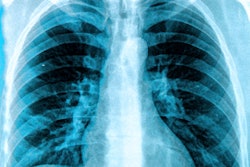

To assess the real-world diagnostic performance of chest x-ray interpretations during the COVID-19 pandemic, the researchers reviewed all patients who had presented to the emergency department at their university hospital between February 24 and April 28 and who had received reverse transcriptase-polymerase chain reaction (RT-PCR) testing and an anteroposterior bedside chest x-ray within 12 hours of admission.

The team then compared the reported chest x-ray results with a reference standard consisting of RT-PCR results as well as information obtained via phone calls to patients who had negative RT-PCR results but did not have a repeated swab test during their hospitalization.

The researchers then assessed diagnostic performance, both overall and over the first and last three weeks of the study. To assess the impact of radiologist experience, they also grouped the seven radiologists in their department by experience levels; three radiologists had less than 10 years of chest x-ray reading experience, while a second group of four had more than 10 years of experience.